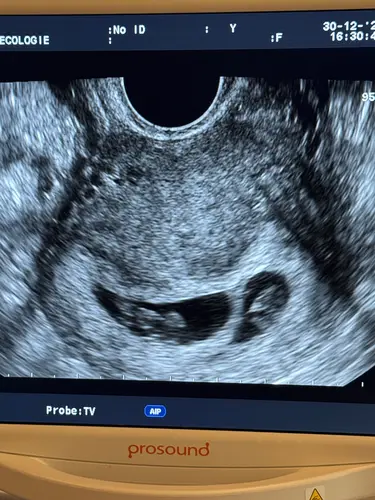

Gister mijn 2e echo gehad. 8 weken 6 dagen, dus nu de 9 aangetikt. De kleine bewoog al lekker door het vruchtwater en een mooi kloppend hartje 😍 over 2 weekjes de termijnecho